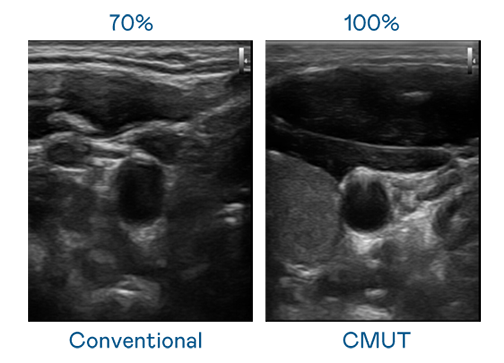

CMUT 技术是一种用电容式微机电元件来产生超音波讯号的技术。与传统 PZT 压电式技术相比,CMUT 频宽增加 30%,更宽频的超音波讯号让影像解析度大幅提升,是实现高影像品质医疗超音波扫描、促进精准医疗发展的关键技术。

大频宽带来超清晰影像

超音波影像的解析度高低,首先取决于探头能发出的讯号频宽。Bodog CMUT 可提供高清晰的超音波讯号,提供高频宽、高灵敏度、影像纹理细节更高的超音波影像,协助医护人员缩短影像判读时间及利用精准的医疗影像进行诊断。